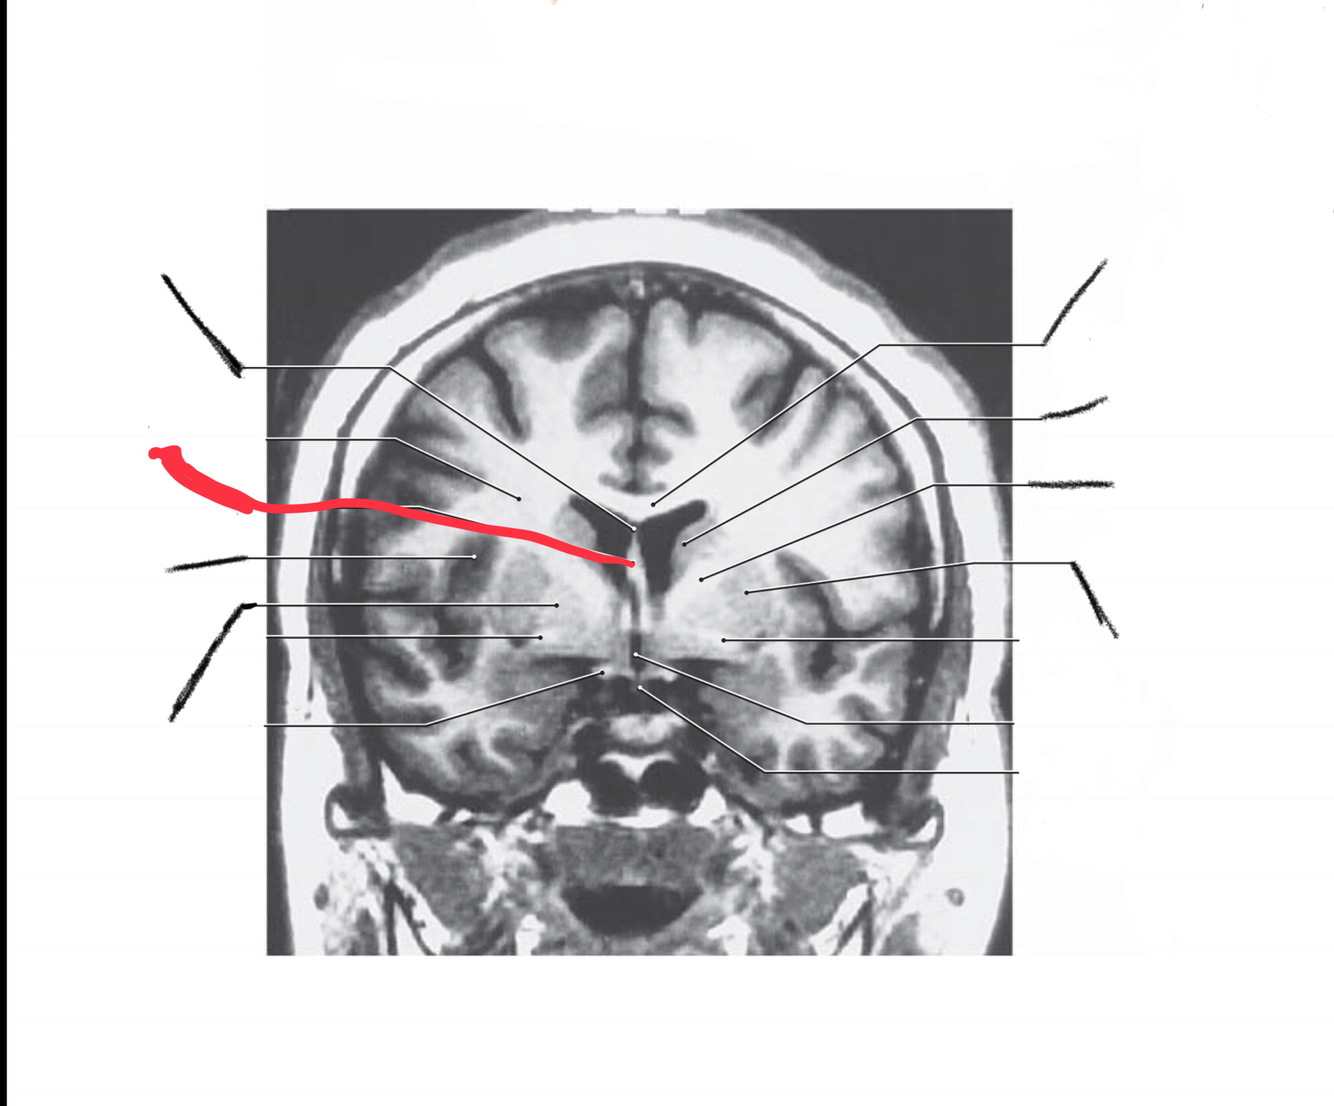

The structure indicated by the red line is?